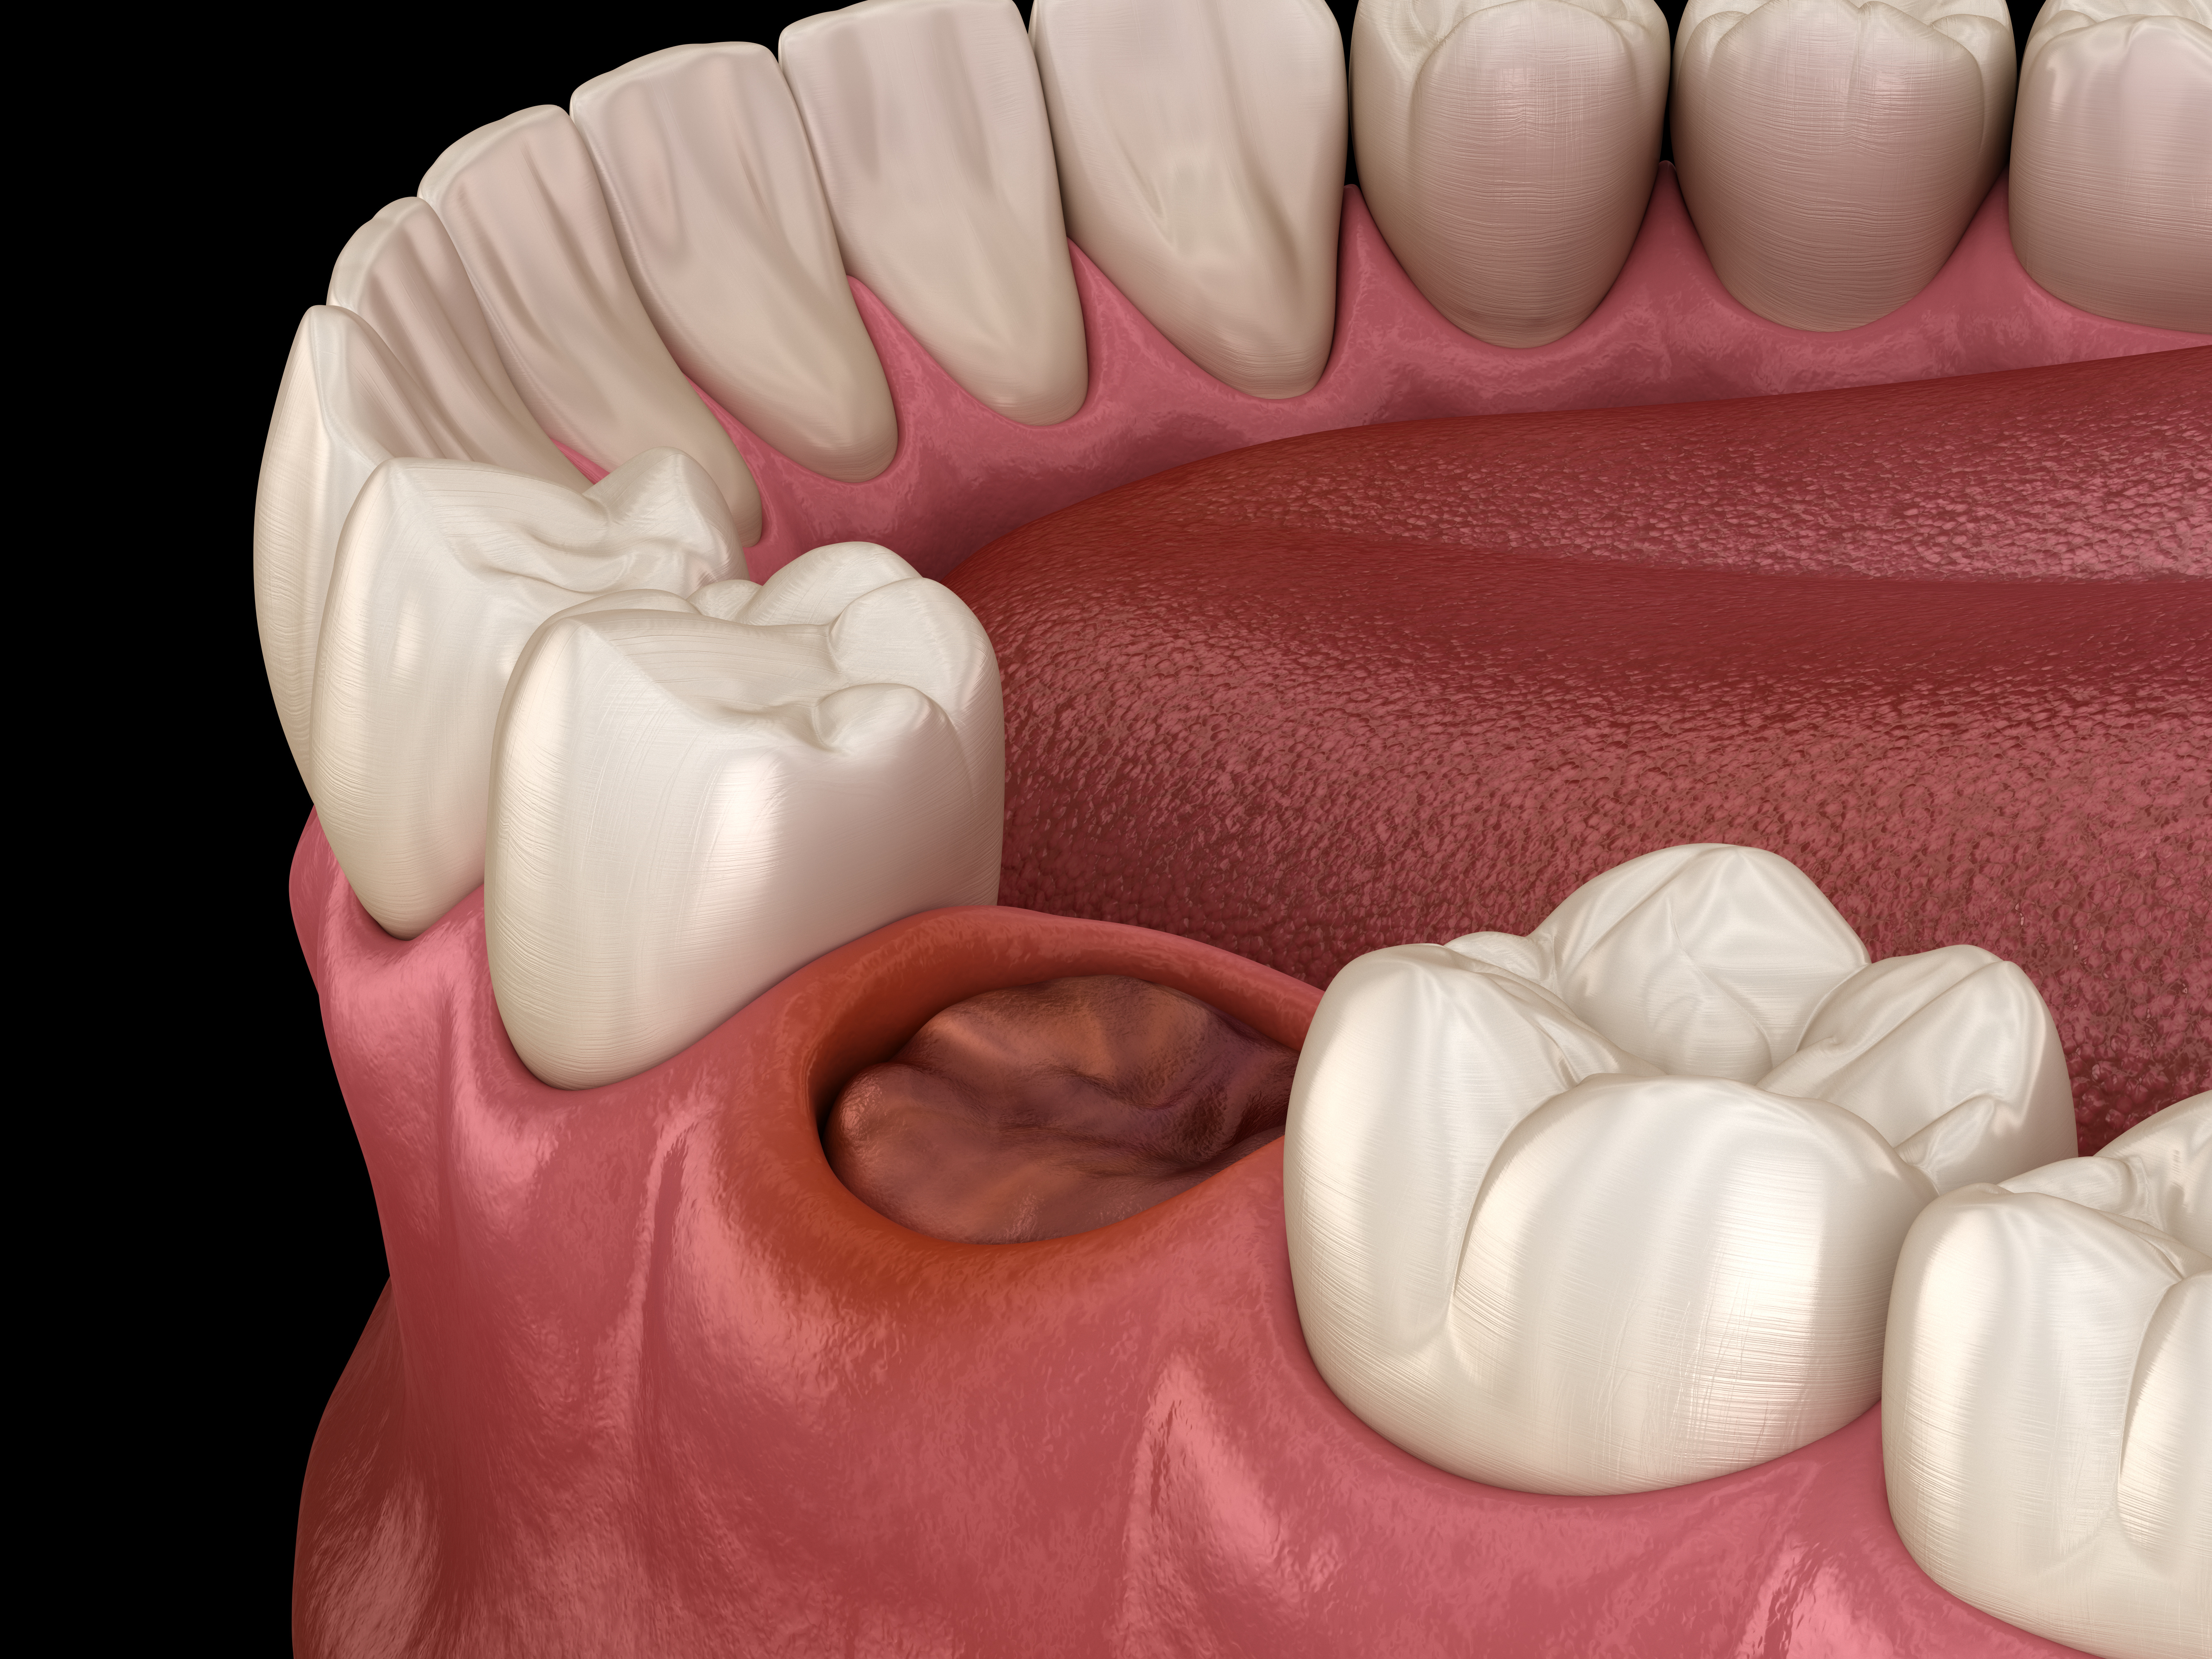

抜歯

残念ながら歯周病によって残せない歯は抜歯となります。精密な診査診断を行った結果、残す価値がない場合は患者様にきちんと説明したうえで、抜歯を行います。